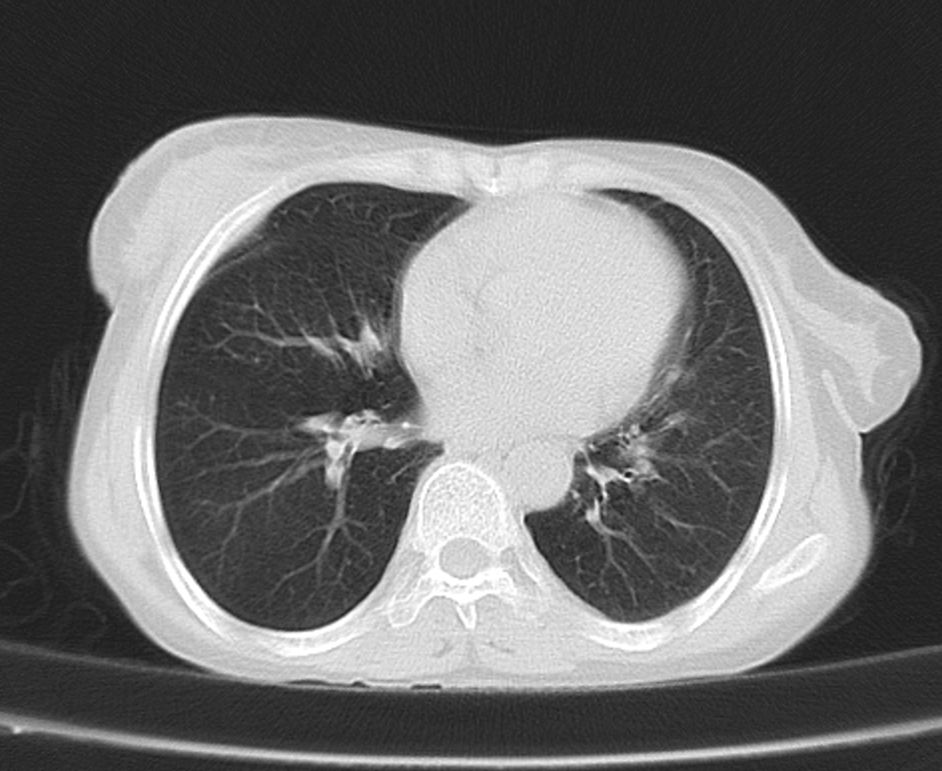

标题: CT21609:右乳包块1年,请各位讨论分析一下,乳腺CA, [打印本页]

标题: CT21609:右乳包块1年,请各位讨论分析一下,乳腺CA,

考虑---右乳癌并胸壁、肋骨、双肺转移。

考虑乳腺癌侵犯肋骨、胸壁及两肺转移可能性大。

右乳癌并胸壁、肋骨、双肺转移。

考虑右侧乳腺癌侵犯肋骨、胸壁及两肺转移。

支持考虑---右乳癌并胸壁、肋骨、双肺转移。

考虑右侧乳腺癌侵犯肋骨、胸壁及两肺转移可能。

考虑右侧乳癌并胸壁、肋骨及双肺多发性转移。